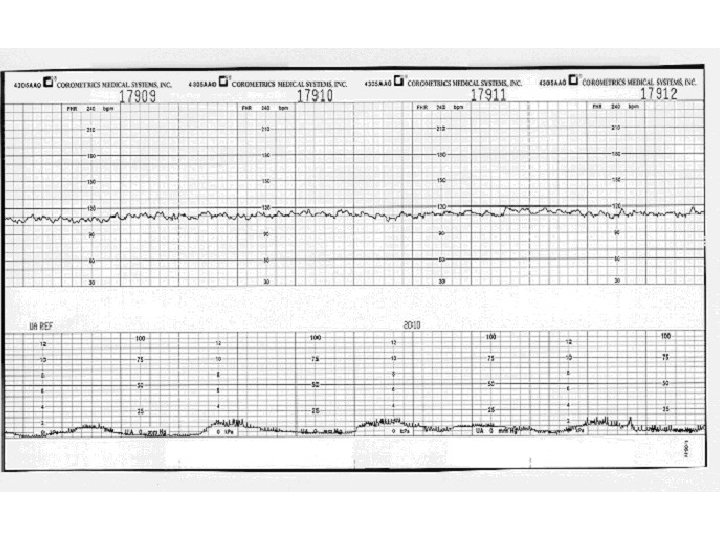

Baseline Fetal Heart Rate The baseline FHR is the heart rate during a 10 minute segment rounded to the nearest 5 beat per minute increment excluding periods of marked FHR variability, periodic or episodic changes, and segments of baseline that differ by more than 25 beats per minute. • The minimum baseline duration must be at least 2 minutes. • If minimum baseline duration is < 2 minutes then the baseline is indeterminate. • Normal baseline = 110 -160 bpm

Baseline Fetal Heart Rate Two Minutes